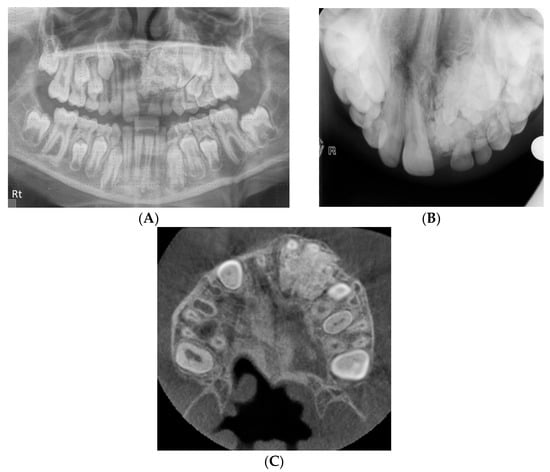

The presence of supernumerary teeth can pose a challenge to the clinician’s ability to distinguish the supernumerary from the true tooth, as illustrated in Figure 4. This case was referred for CBCT to differentiate the true lateral incisor tooth and the supplemental tooth. The supplemental lateral incisor was identified as the palatally positioned tooth, following a CBCT assessment of the more rudimentary tooth morphology. Precise morphological measurements and accurate localisation of teeth from CBCT images allow the clinician to make an informed decision on which tooth to extract and the optimal surgical approach to reduce the risk of damage to the true tooth.

Figure 4.

(A) The upper standard occlusal shows a supplemental tooth in the maxillary left lateral incisor area. It is difficult to discern from the conventional views which of the two teeth, marked with a white and a black asterisk would be morphologically optimal to serve as the lateral incisor. (B) CBCT axial view of the left maxilla. An analysis of the dimensions of the teeth revealed that the tooth marked with the white asterisk was smaller compared to the adjacent unerupted tooth and the contralateral lateral incisor, and as such, more likely to represent the supplemental lateral incisor.